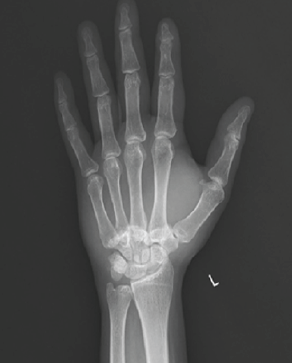

Letter to the Editor: Revisiting the “Ice Cream Scoop” Sign in Adult Elbow Tuberculosis: Extending Beyond the Pediatric Population

Nadeem Akhtar Qureshi

………………………………p.555-556